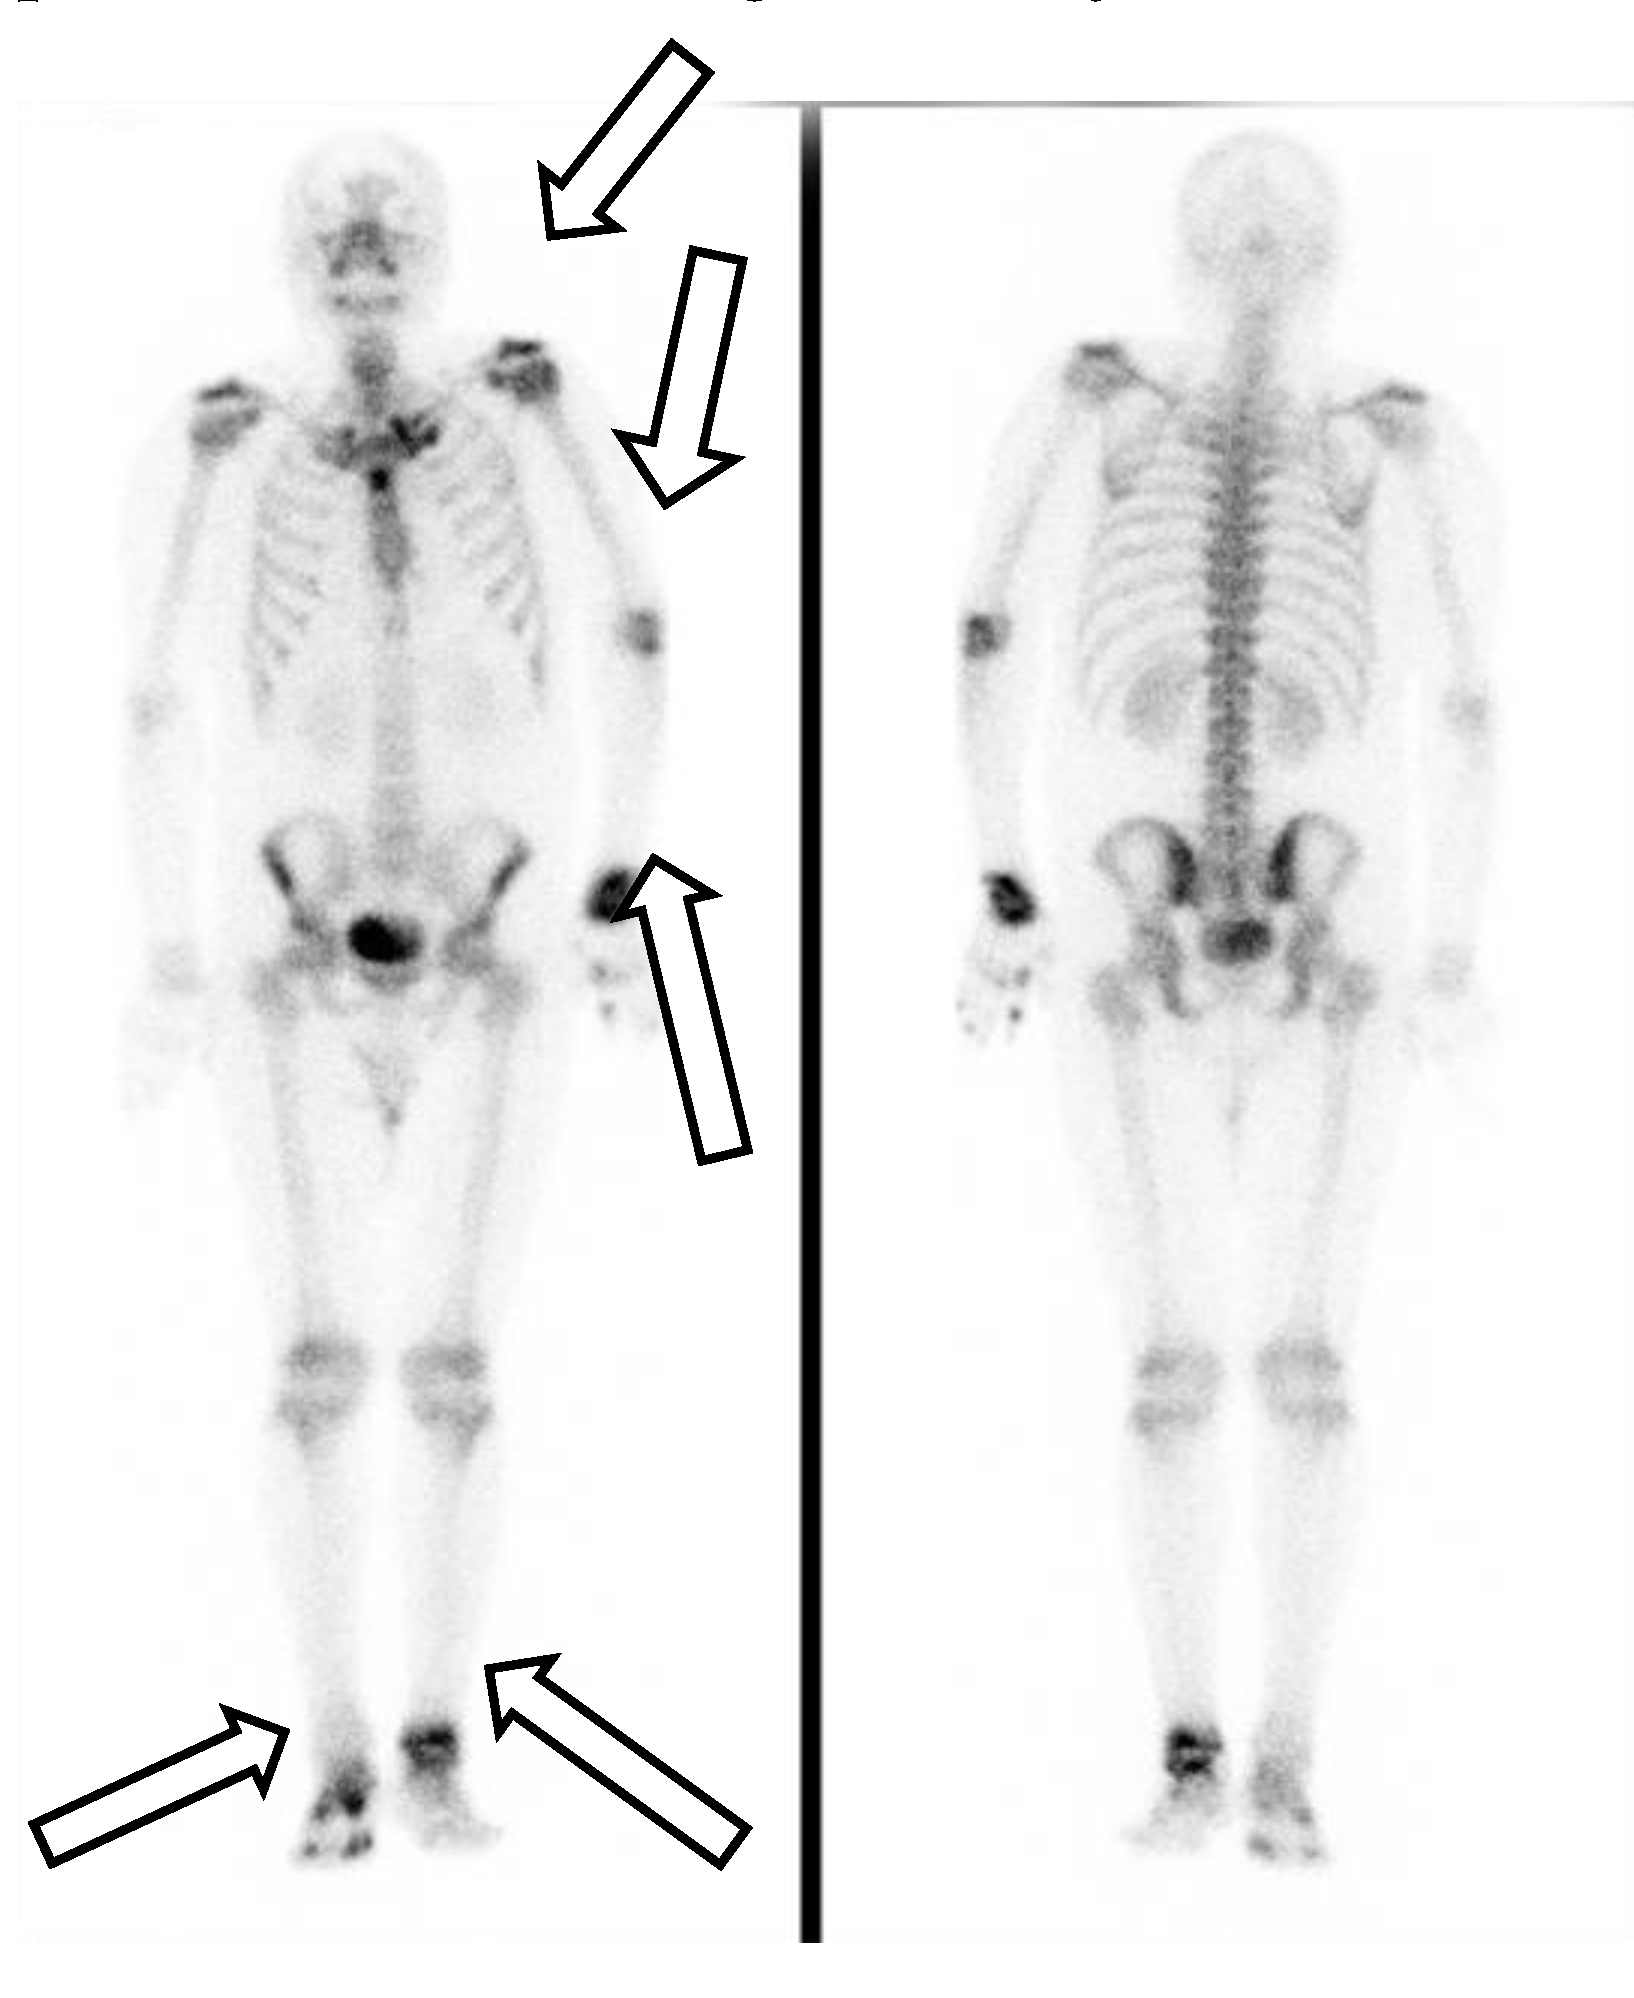

His first admission was to the division of infectious diseases. The 2019 novel coronavirus disease (COVID-19) had been excluded after repeated blood sampling and plain X-ray films of the chest. Blood tests showed a white blood cell count of 12,850 cells/mm3, hemoglobin level of 13.3 g/dL, platelet count of 490,000 cells/mm3, plasma creatinine level of 1.0 mg/dL, alanine aminotransferase (ALT) level of 79 U/L, aspartate aminotransferase (AST) level of 38 U/L, and c-reactive protein (CRP) level of 15.00 mg/L. Serum tests did not identify viral hepatitis infection. Microbiology examination of the sputum, blood, urine, and feces did not identify any pathogens. Blood sampling did not detect any autoantibodies. Physical examination did not reveal abnormal murmurs of the heart or abnormal primitive neurologic reflexes. Plain X-ray films of the chest did not show mass lesions or abnormalities in the lungs. X-ray of the major joints of all limbs did not show fracture, erosion of bones, or abnormalities of soft tissue. A technetium-99m methylene diphosphonate bone scan revealed increased uptake in the left shoulder, elbow, wrist, and ankle, and right foot and toes, which was compatible with the clinically significant arthritis noted in the physical examination (Figure 1). The patient’s fever did not respond to antibiotics for 2 weeks from the first admission. Reactive arthritis was suspected initially because no significant pathogens or autoantibodies had been identified, and sterile inflammation was suspected. The fever responded to daily systemic methylprednisolone (40 mg), and the patient was discharged 17 days after the first admission.

However, polyarthritis in both wrists, metacarpophalangeal joints, knee joints, and ankles developed one week after the patient’s first discharge from the hospital. Physical examinations on the second admission revealed an alert consciousness without abnormal neurologic reflexes. A gallium-67 tumor scan indicated inflammation in the left shoulder, left sternoclavicular junction, left interscapular region, lateral right hip region, left buttock, right knee, and left ankle, but no evidence of malignancy (Figure 2).

Figure 1. A technetium-99m methylene diphosphonate bone scan revealed increased uptake in the left shoulder, elbow, wrist, and ankle, and right foot and toes.

Figure 2. A gallium-67 tumor scan indicated inflammation over left shoulder, left sternoclavicular junction, left interscapular region, lateral right hip region, left buttock, right knee, and left ankle, but no evidence of malignancy.